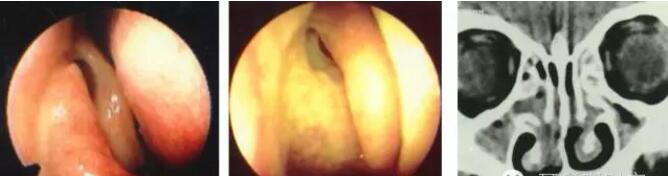

中鼻甲解剖变异:泡状中鼻甲

泡状中鼻甲感染及引起上颌窦口阻塞

中鼻甲解剖变异:中鼻甲反向弯曲

中鼻甲解剖变异与鼻窦炎

鼻中隔偏曲

高位弯曲压迫中鼻甲

同侧中鼻道、嗅沟引流障碍

阻塞性鼻窦炎